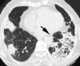

Bronchiolectasis

Usual interstitial pneumonia (UIP) is a form of lung disease characterized by progressive scarring of both lungs. The scarring (fibrosis) involves the supporting framework (interstitium) of the lung. [Source: Wikipedia ]